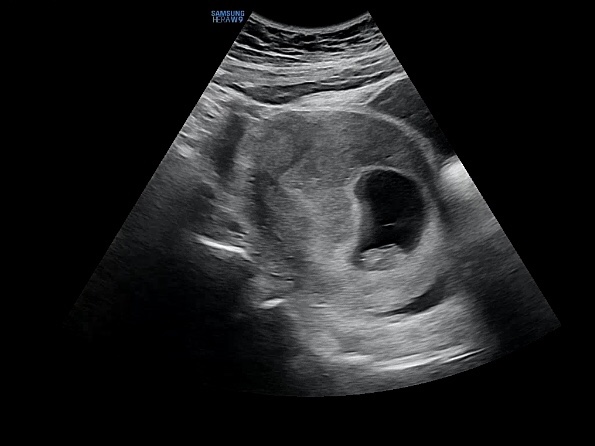

22.5.6 8주1일

첫방문 이후 4주뒤에 찾은 정기검진 날! 8주에는 손이랑 발이 조금씩 생겨서 하리보 젤리 모양의 초음파를 ...